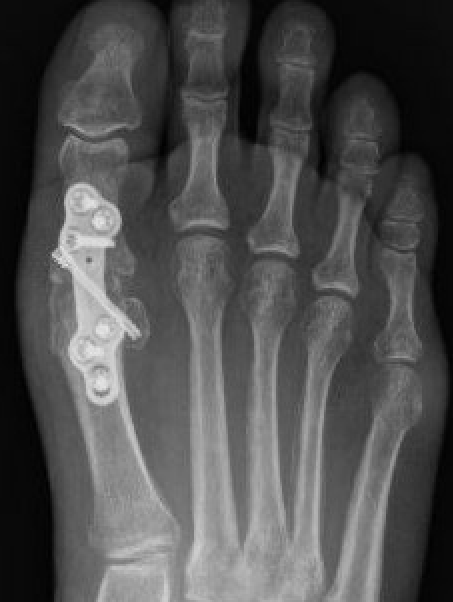

Fixation with screws

Scarf osteotomy + DSTP

Indications

- moderate hallux valgus